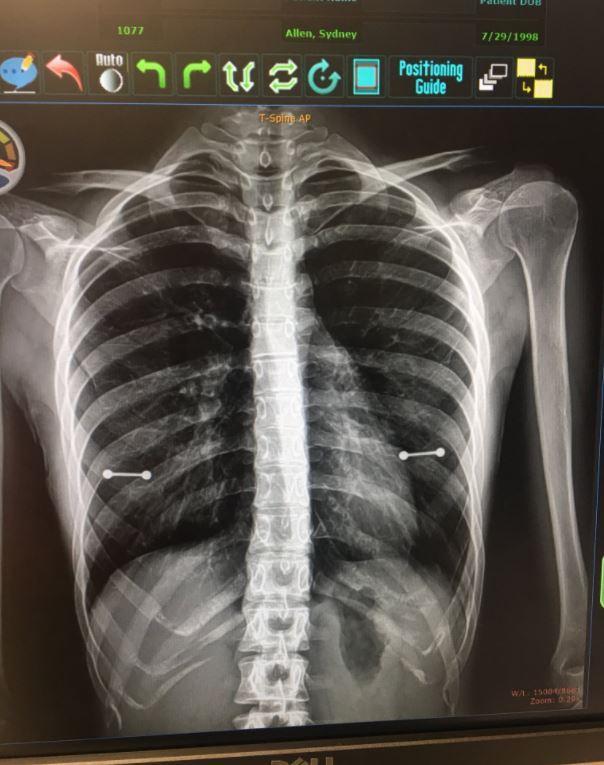

▼雖然這位美國母親比較保守,一向不能接受孩子刺青和在身體打洞,沒想到她的20歲女兒西妮(Sydney Allen)卻因為一張X光照而讓秘密不小心曝光!

▼原來西妮最近被發現罹患了脊髓空洞症(Syringomyelia),必須持續追蹤檢查以便進行治療矯正,不過這次醫生對她進行X光檢查時,因為忘了提醒必須將所有穿孔飾品拿掉,讓X光照清楚的拍出她的乳房處有2條「金屬槓」,雖然醫生和護理師看了之後當場大笑,不過陪同在旁的母親卻是一秒變臉,生氣的向女兒表示「我們等下來討論一下這個問題」。

▼原來這個乳環是西妮在今年6月時和閨蜜一起去穿的「生日禮物」,不過媽媽並不知情。之後西妮也在自己的推特上寫道「今天我媽媽發現我在乳頭打洞了」,同時附上X光的照片,很快就吸引了超過20萬名網友按讃!